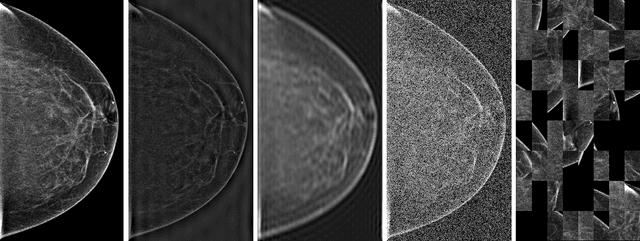

Abstract:Deep neural networks (DNNs) show promise in breast cancer screening, but their robustness to input perturbations must be better understood before they can be clinically implemented. There exists extensive literature on this subject in the context of natural images that can potentially be built upon. However, it cannot be assumed that conclusions about robustness will transfer from natural images to mammogram images, due to significant differences between the two image modalities. In order to determine whether conclusions will transfer, we measure the sensitivity of a radiologist-level screening mammogram image classifier to four commonly studied input perturbations that natural image classifiers are sensitive to. We find that mammogram image classifiers are also sensitive to these perturbations, which suggests that we can build on the existing literature. We also perform a detailed analysis on the effects of low-pass filtering, and find that it degrades the visibility of clinically meaningful features called microcalcifications. Since low-pass filtering removes semantically meaningful information that is predictive of breast cancer, we argue that it is undesirable for mammogram image classifiers to be invariant to it. This is in contrast to natural images, where we do not want DNNs to be sensitive to low-pass filtering due to its tendency to remove information that is human-incomprehensible.